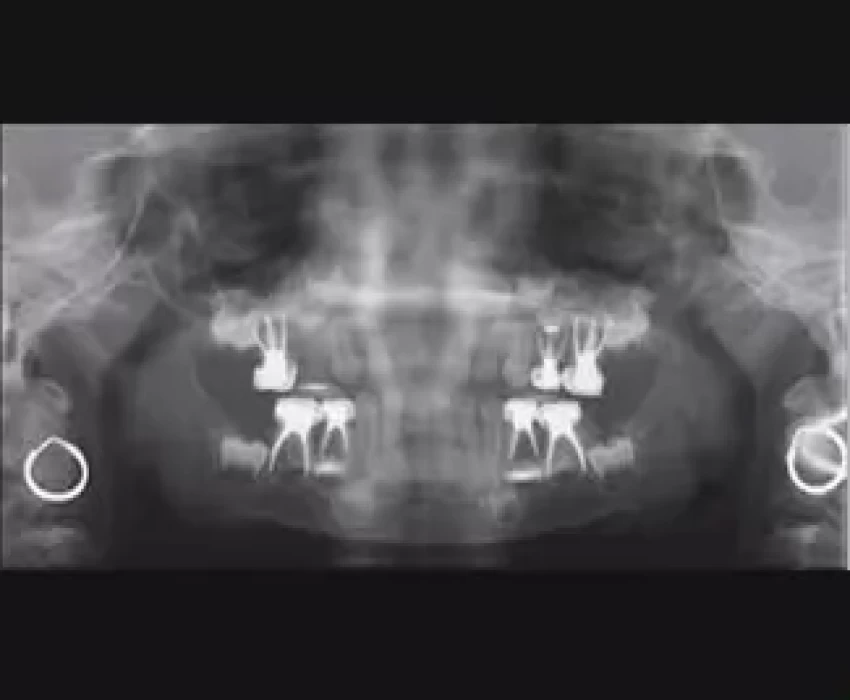

Despite the dental profession's emphasis on prevention, threats to pulp survival, such as caries, restorative dental treatment, and traumatic injuries, have not been eliminated. As a consequence, children continue to lose teeth prematurely, and procedures aimed at preventing and treating pulp disease in the primary and immature permanent dentitions remain an integral part of contemporary dental practice. Some may question why efforts to preserve pulpally involved primary teeth are important. These practitioners maintain that such efforts may present a risk to developing permanent successors and, in any case, the primary teeth will be lost before long. Preservation of arch space is one of the principal objectives of pediatric dentistry. Premature loss of primary teeth may cause aberration of the arch length, resulting in mesial drift of the permanent teeth and consequent malocclusion. Whenever possible, the tooth with pulp involvement should be maintained within the dental arch in a functional and disease-free condition. Other objectives of preserving the primary teeth are to safeguard aesthetics and mastication, prevent aberrant tongue habits, aid in speech, and prevent the psychological effects that may be associated with tooth loss. Premature loss of the maxillary incisors before 3 years of age has been shown to cause speech impairment that may persist in later years.

It is equally undesirable for children to suffer the unplanned loss of permanent teeth, and it should be noted that the prognosis for lifelong retention of an immature tooth with a short root and fragile dentinal walls is far worse than for a mature permanent tooth. Special treatments for the immature permanent tooth, therefore, focus on preserving vital pulp functions, at least until dental development is complete